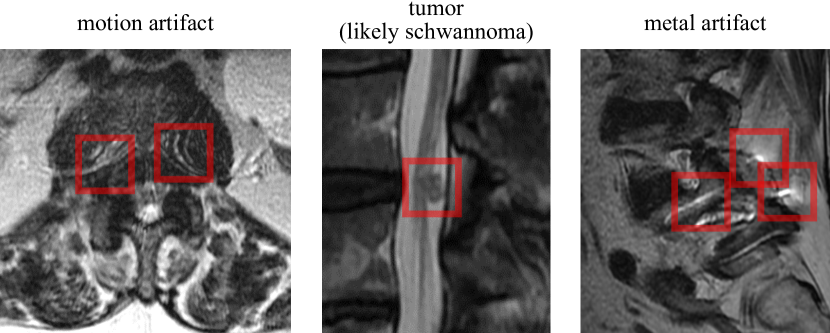

To investigate the clinical utility of Ordinal APS to enhance AI-augmented workflows, we evaluate one possible clinical integration use case: flagging low confidence predictions (i.e. ones with a large set size). The radiologist’s performance and user experience of the model may be improved by raising their awareness of those instances in which the model performance may be degraded by scan anomalies or when uncertainty quantification is very high, excluding such potentially poor quality results from their review responsibilities altogether. We define an uncertainty score for each patient by taking the average set size for all disc levels and grading tasks. An neuroradiologist with >20absent20>20 years of experience determined what constituted a “significant imaging anomaly” within the context of spinal stenosis interpretation.

Refer to caption

Figure 7: Three anomalies found in high uncertainty predictions; the anomalous areas are boxed in red.

As a statistical validation of these results, we examined the report of 70 cases with the highest uncertainty and found 17 such anomalies: 11 cases with artifacts from metallic orthopedic hardware, four cases with motion artifacts, one case with a large tumor occupying the spinal canal, and one case with a severe congenital abnormality (achondroplastic dwarfism). In contrast, a random sample of 70 cases from the dataset only demonstrated five cases with significant anomalies which were all orthopedic hardware artifacts. This difference is significant with p<0.05𝑝0.05p<0.05 by Fisher’s exact test, and qualitatively the abnormalities found in the filtered samples were more extreme.